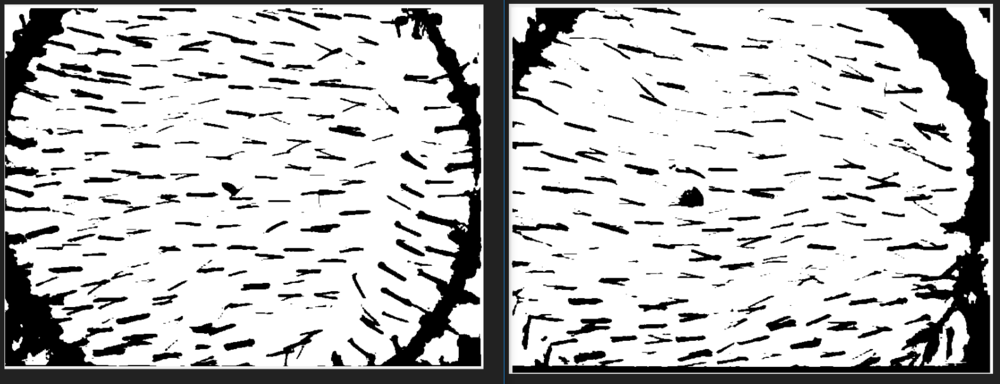

The famous replicel phase one trial pictures a little.

right bevore and left after 6 months...

I converted the pictures to black and white (255 grey steps) then i applied a threshold to have a clear cut.

I hoped I could see with this technic some vellus hair turn into terminal... But from this pictures it seems the opposite is true ???

I am with you, bro. It seems to me the "after" photo show less terminal and more vellus hair. tbh, the left looks better than the right, even though it seems from their word that the right is better than the left.

Huh ? Are you serious ? Dont get me wrong but it seems to my eyes that there is less terminal hair in the "after" image even the number say otherwise. @That Guy, any comment from you ? Seriously

And therefore i m wondering how they can say in this particular picture the terminal hair increased by 14.5%.

Look in both picture at the hair direct above the first tatoo. In the bevore picture these hair seem sicker.

During my studies i gathered some knowledge on data evaluation. That is why I made evaluate the picture how I would do it. And I m quite surpsrised with the result.

Yes but they got the data by evaluating the picture.

And looking at the terminal hair before and after this seems more like a decrease than increase.